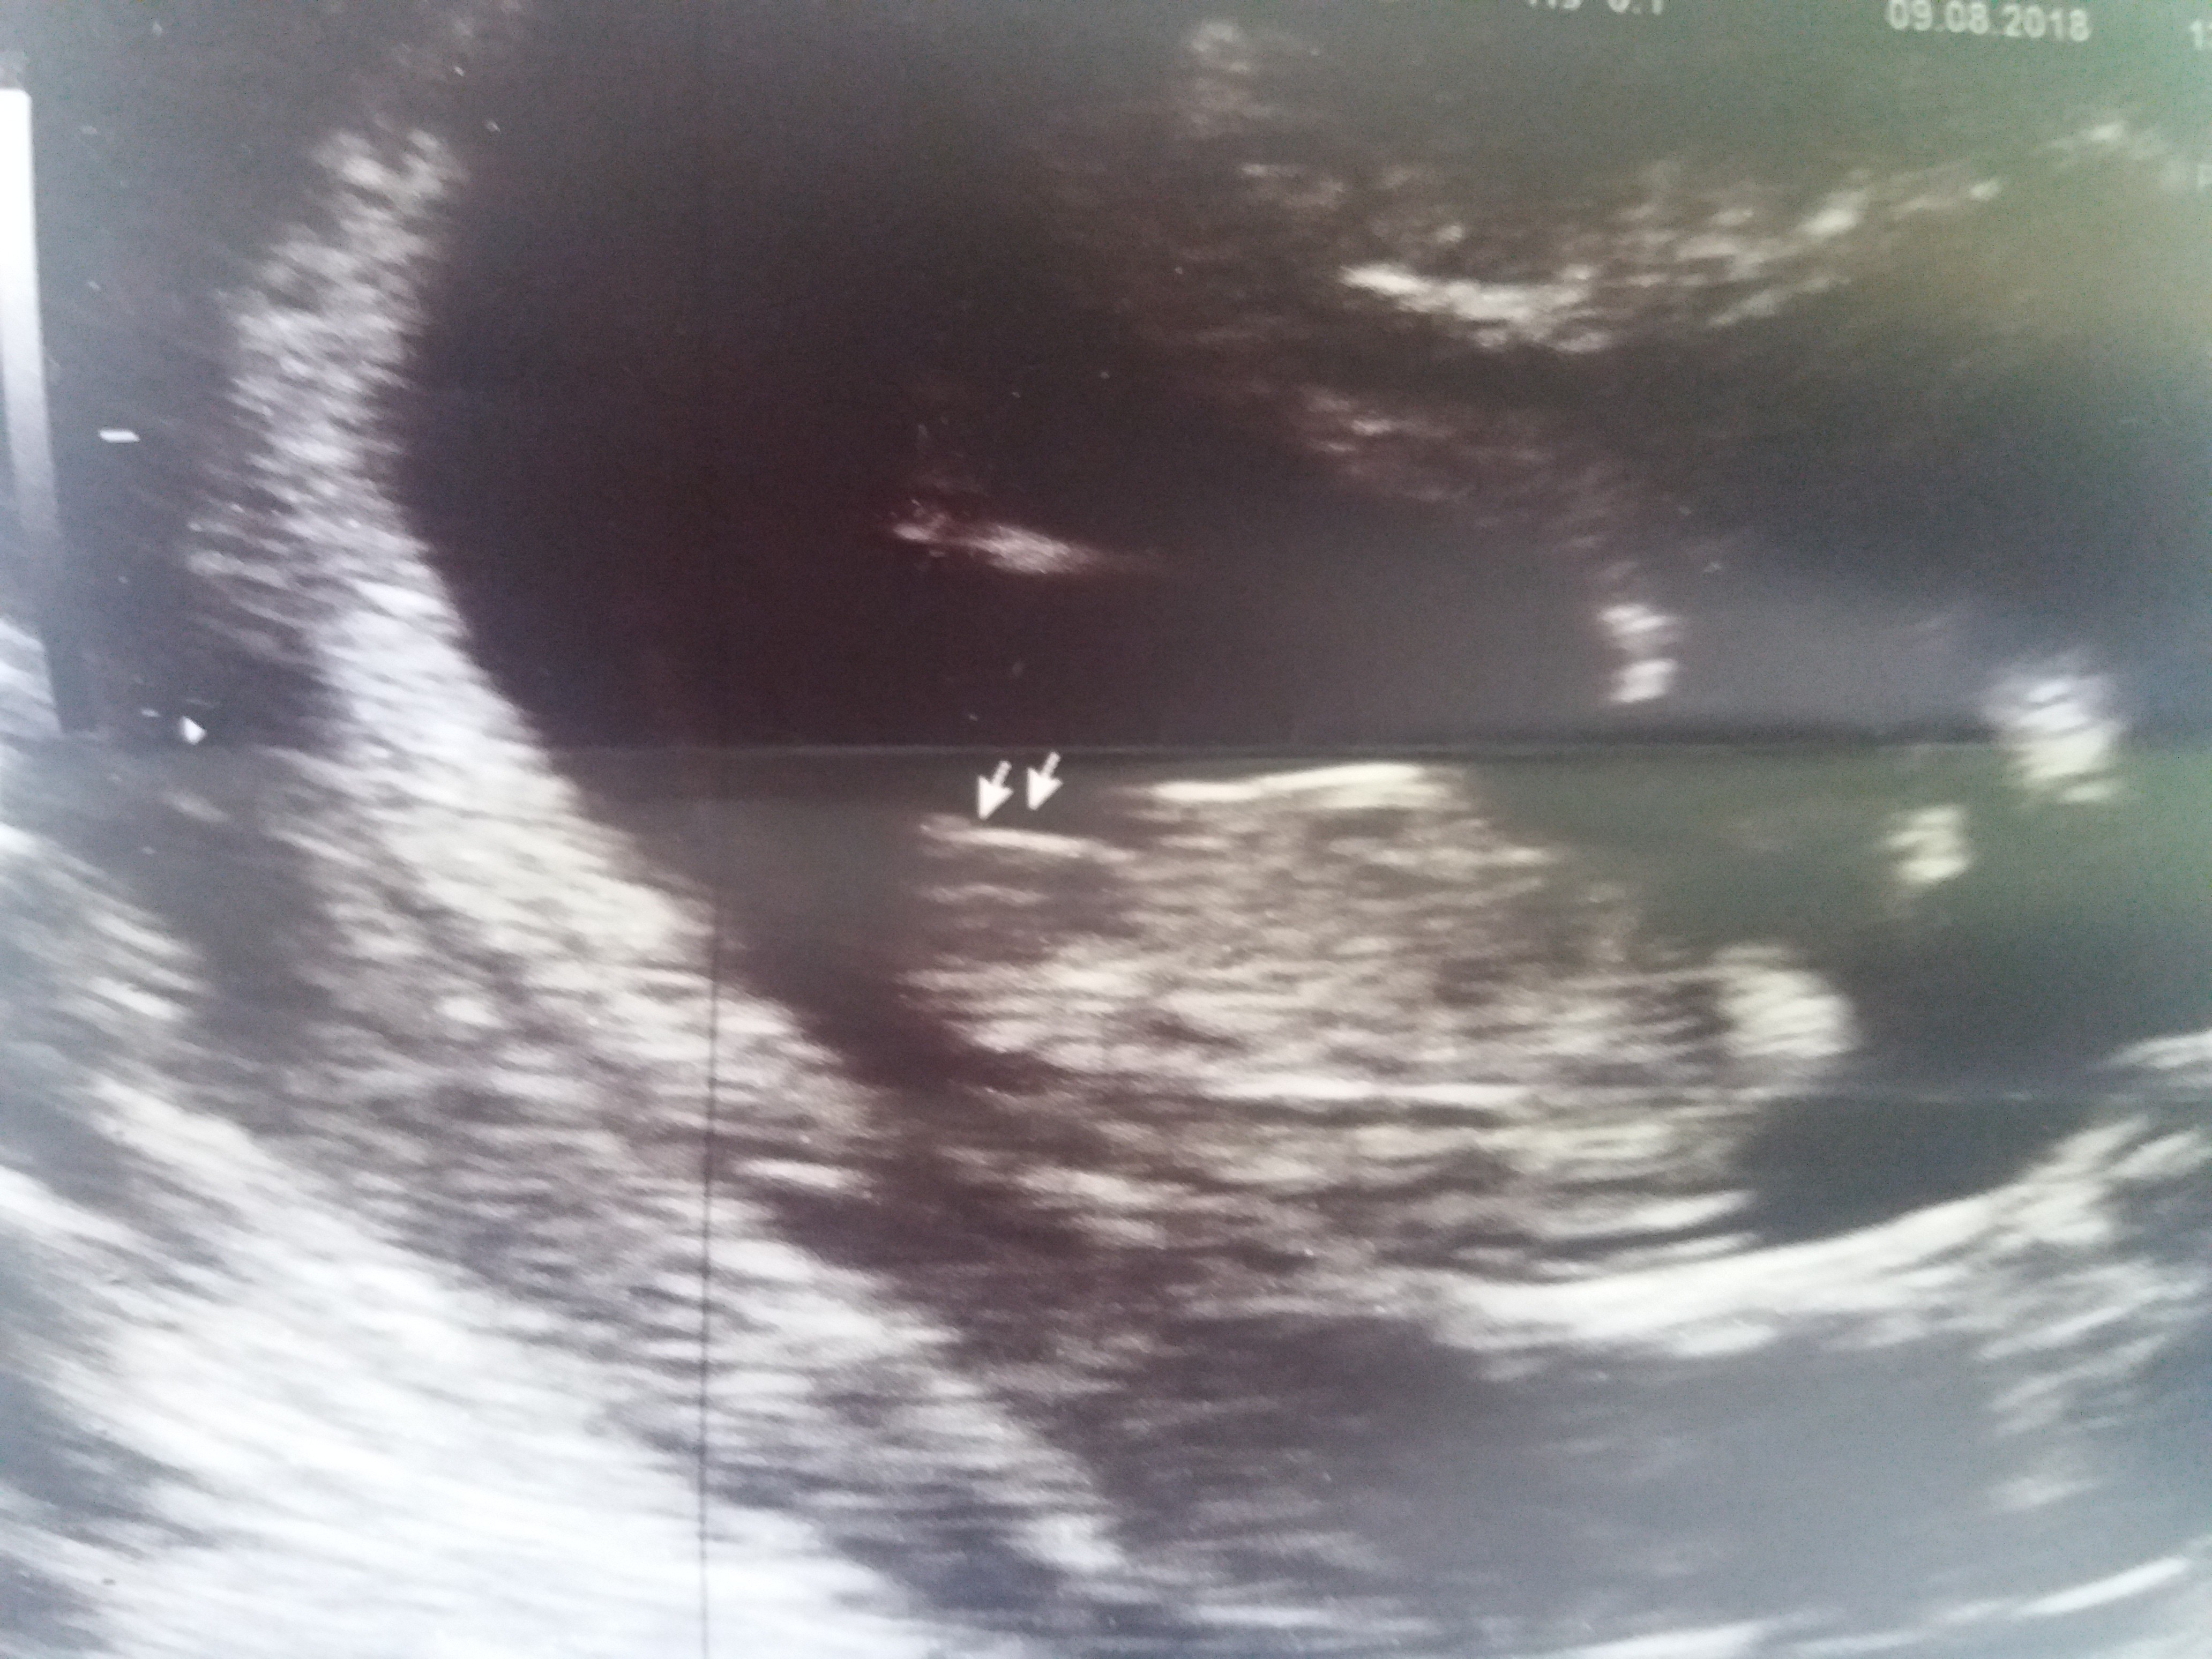

Ja po wczorajszych prenatalnych Troszkę się zestresowałam i o nic nie zapytałam-prócz płci, której Pani doktor nie określiła. Faktycznie kiepsko widać "dół". A Wy coś dostrzegacie?

Najważniejsze jednak, że maluch jest zdrowy i wszystko ok Oceniana czaszka, mózg, nosek, crl, nt, kręgosłup, serduszko, tętnice, pępowina, żołądek, wątroba, pęcherz, rączki, nóżki, paluszki... wszystko prawidłowe. Różnica z OM a USG to jeden dzień do przodu wg USG - wahamy się ciaglę z terminem od 14.02 do 16.02 Mega ruchliwy ten nasz człowieczek, ciągle drapał się po główce, kręcił i trzeba było go szukać Mąż jak najbardziej obecny przy badaniu Robiłam jeszcze krew, ale na ten wynik będę jeszcze czekać do 14. dni roboczych. Wg OM - 12+6, USG - 13+0, CRL 6.62 cm, NT 1.60 mm. Pomiary liczone dwukrotnie. Serduszko 157/163 - mierzone kilkukrotnie w jamie i tętnicach. Wstawiam zdjęcia i wyniki. Wszystko było ok, ale może któraś z Was potrafi je jeszcze ocenić i odczytać i służy dobrą radą? Szkoda tylko, że ani na chwilkę nie włączone 3D.